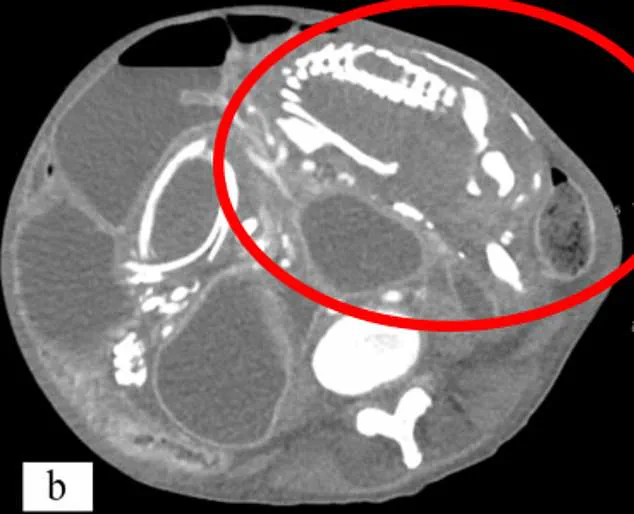

When an ectopic pregnancy fails, the body typically reabsorbs the tissue. However, if the fetus is more than 12 weeks old, its bony skeleton cannot be reabsorbed. The immune system then calcifies the tissue, creating a hardened mass. This process, a form of mummification, can leave the lithopedion undetected for decades. Dr. Lee notes that only 1.5 to 1.8% of ectopic pregnancies progress to lithopedion, and the condition is often asymptomatic for years. However, when symptoms do arise, they may include chronic abdominal pain, urinary frequency, or constipation due to pressure on surrounding organs. Infections can also develop, leading to abscesses.

Historically, the earliest known lithopedion was discovered in an archaeological site in Texas, dating back to 1100 BC. Modern cases continue to surface. In Brazil, an 81-year-old woman died after a scan revealed a lithopedion she had carried for 56 years. The fetus, discovered during a routine examination for stomach pain, had been present since her last pregnancy over five decades earlier. Such cases, while rare, underscore the importance of early detection and medical intervention.